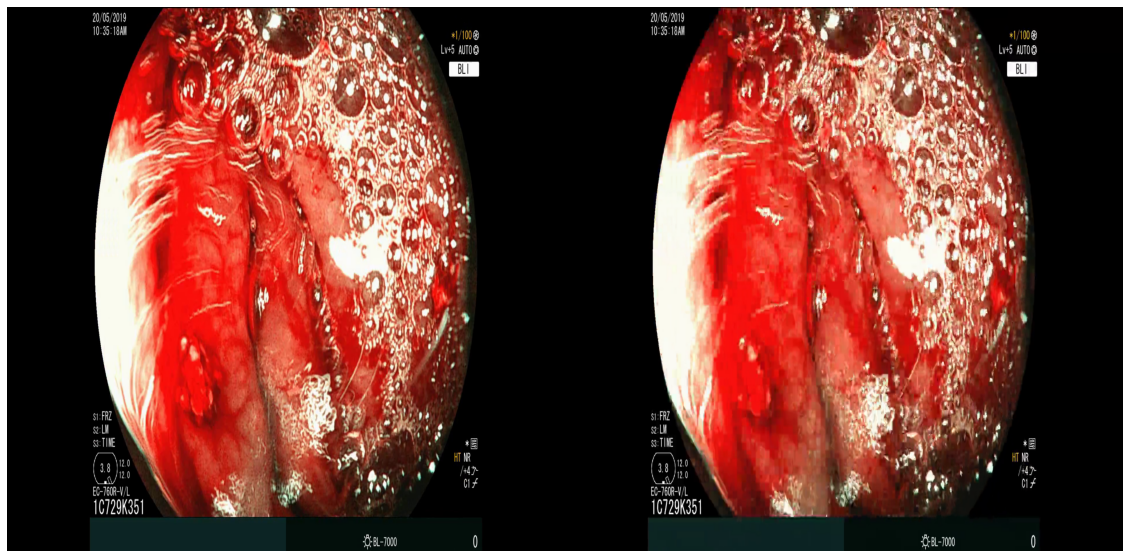

Compression quality: Figure 1 (middle) shows the compression rate versus frame quality distribution for H264 and HEVC. Importantly, we see that H264 and HEVC compress the most medically relvant frames statistically significantly worse: treating each QP value separately, a two-sided Kolmogorov-Smirnov test between distribution of PSNR-CbCr shows that the frame quality is lower for polyp frames than for all frames. For each QP value, , , H264 (HEVC) maximum p-value over all tests is (), mean test statistic (). For the same test with PSNR-Y, see the Appendix. Figure 2 top two rows show the lowest quality compressed frames inside the body according to PSNR-CbCr, with and without polyps (for the absolute worst quality compressed frames, see the Appendix).

A.3 Lowest quality compressed frames